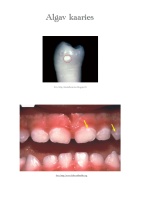

Suutervis

koolis